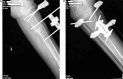

A) X-ray imaging of the injured tibia was performed 4 months after the initial application of external fixation, B) X-ray imaging of the injured limb after external fixation was remounted